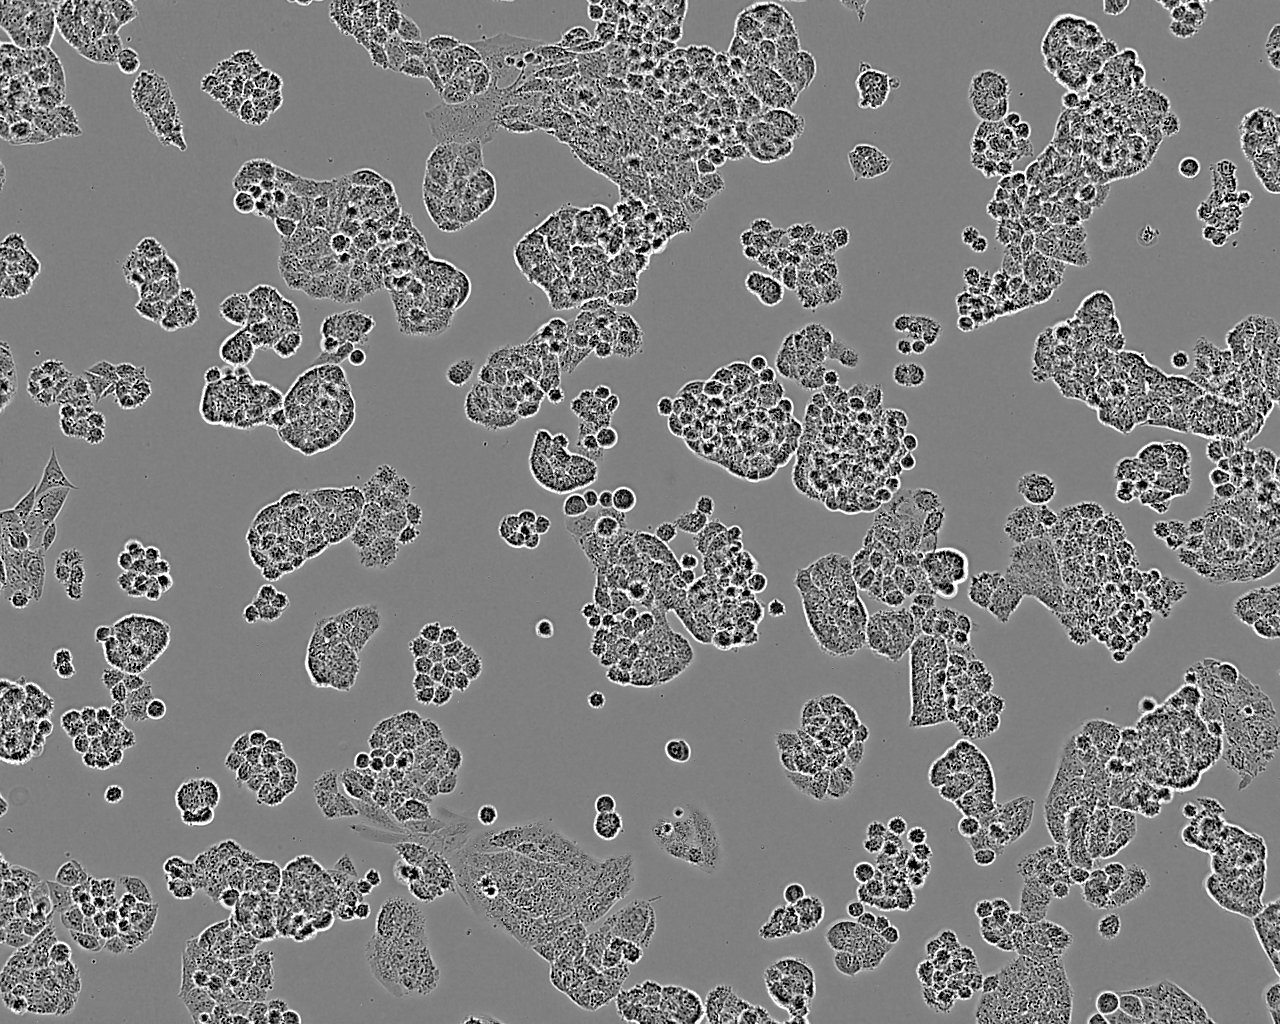

特征特性 从一位未接受治疗的患者的癌组织中分离建系。细胞会单层生长,在摇床培养时可悬浮生长。可用作抗药药物敏感性研究模型。

形态特征 上皮细胞样

生长特征 贴壁